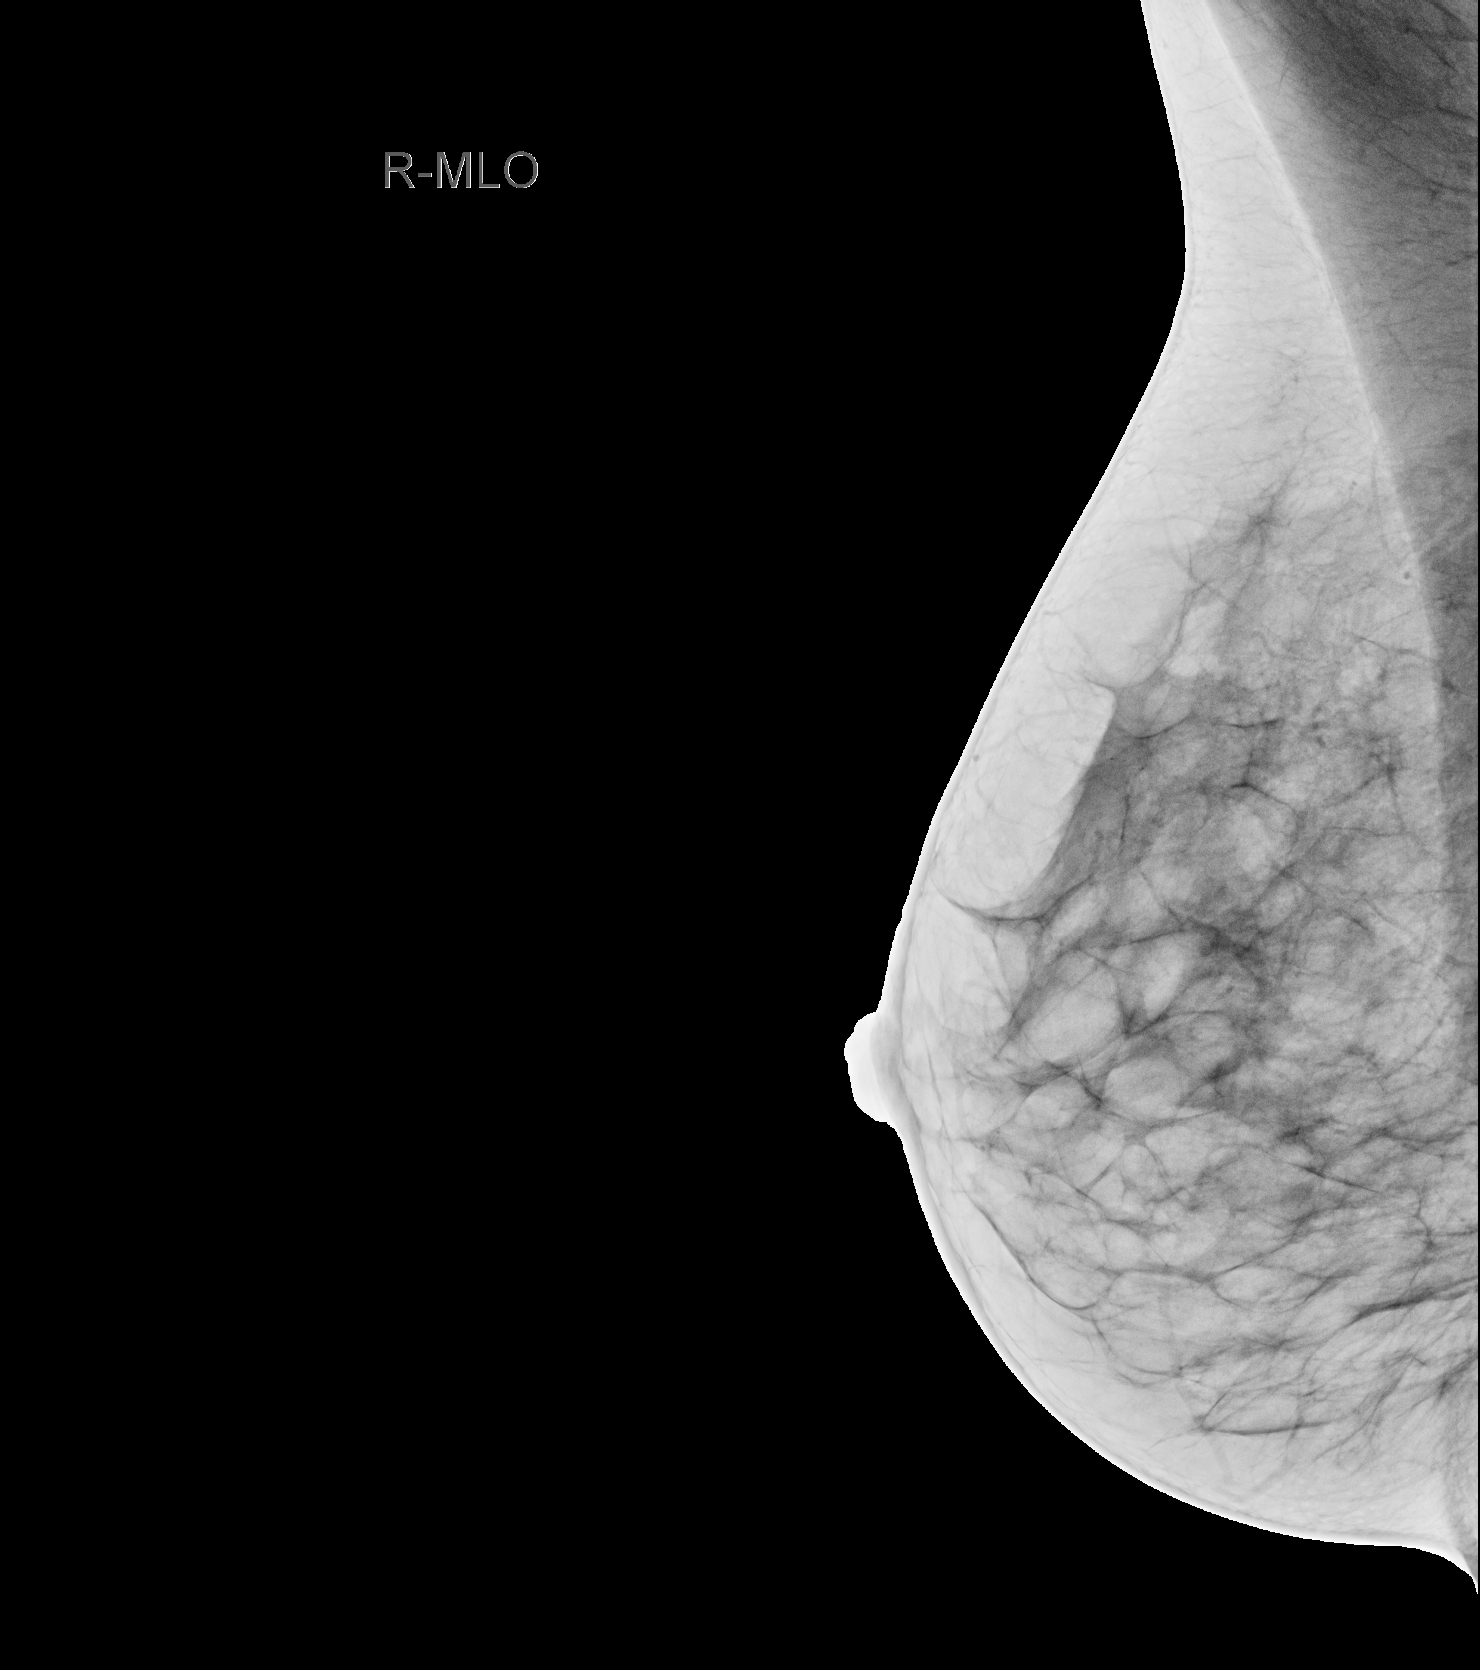

Die Mammographie ist eine Röntgenuntersuchung der Brust. Sie wird mit einem digitalen Vollfeldsystem durchgeführt. Die Untersuchung wird im Rahmen des Brustkrebsfrüherkennungsprogramms bei Frauen ab dem vierzigsten Lebensjahr empfohlen. Auch bei Beschwerden oder familiärer Vorbelastung wird je nach Anamnese eine Mammographie durchgeführt.

Das neue Mammographiesystem „Mammomat Revelation“ der Firma Siemens Healthineers, mit dem einzigartigen Tomosyntheseverfahren, ermöglicht uns eine höhere Entdeckungsrate von Brustkrebs bei geringerer Strahlendosis. Bei der Mammographie werden von jeder Brust zwei Aufnahmen in verschiedenen Ebenen angefertigt. Die Brust wird dabei leicht dosiert komprimiert, um eine optimale Bildqualität bei geringster Strahlenbelastung zu erreichen. Zusätzlich besteht die Möglichkeit einer Tomosynthese, die überwiegend bei dichtem Drüsengewebe eingesetzt wird. Diese neue Technologie ermöglicht uns eine Schichtbildaufnahme der Brust, wodurch ein 3D-Eindruck entsteht und somit wird die Diagnosegenauigkeit erhöht.